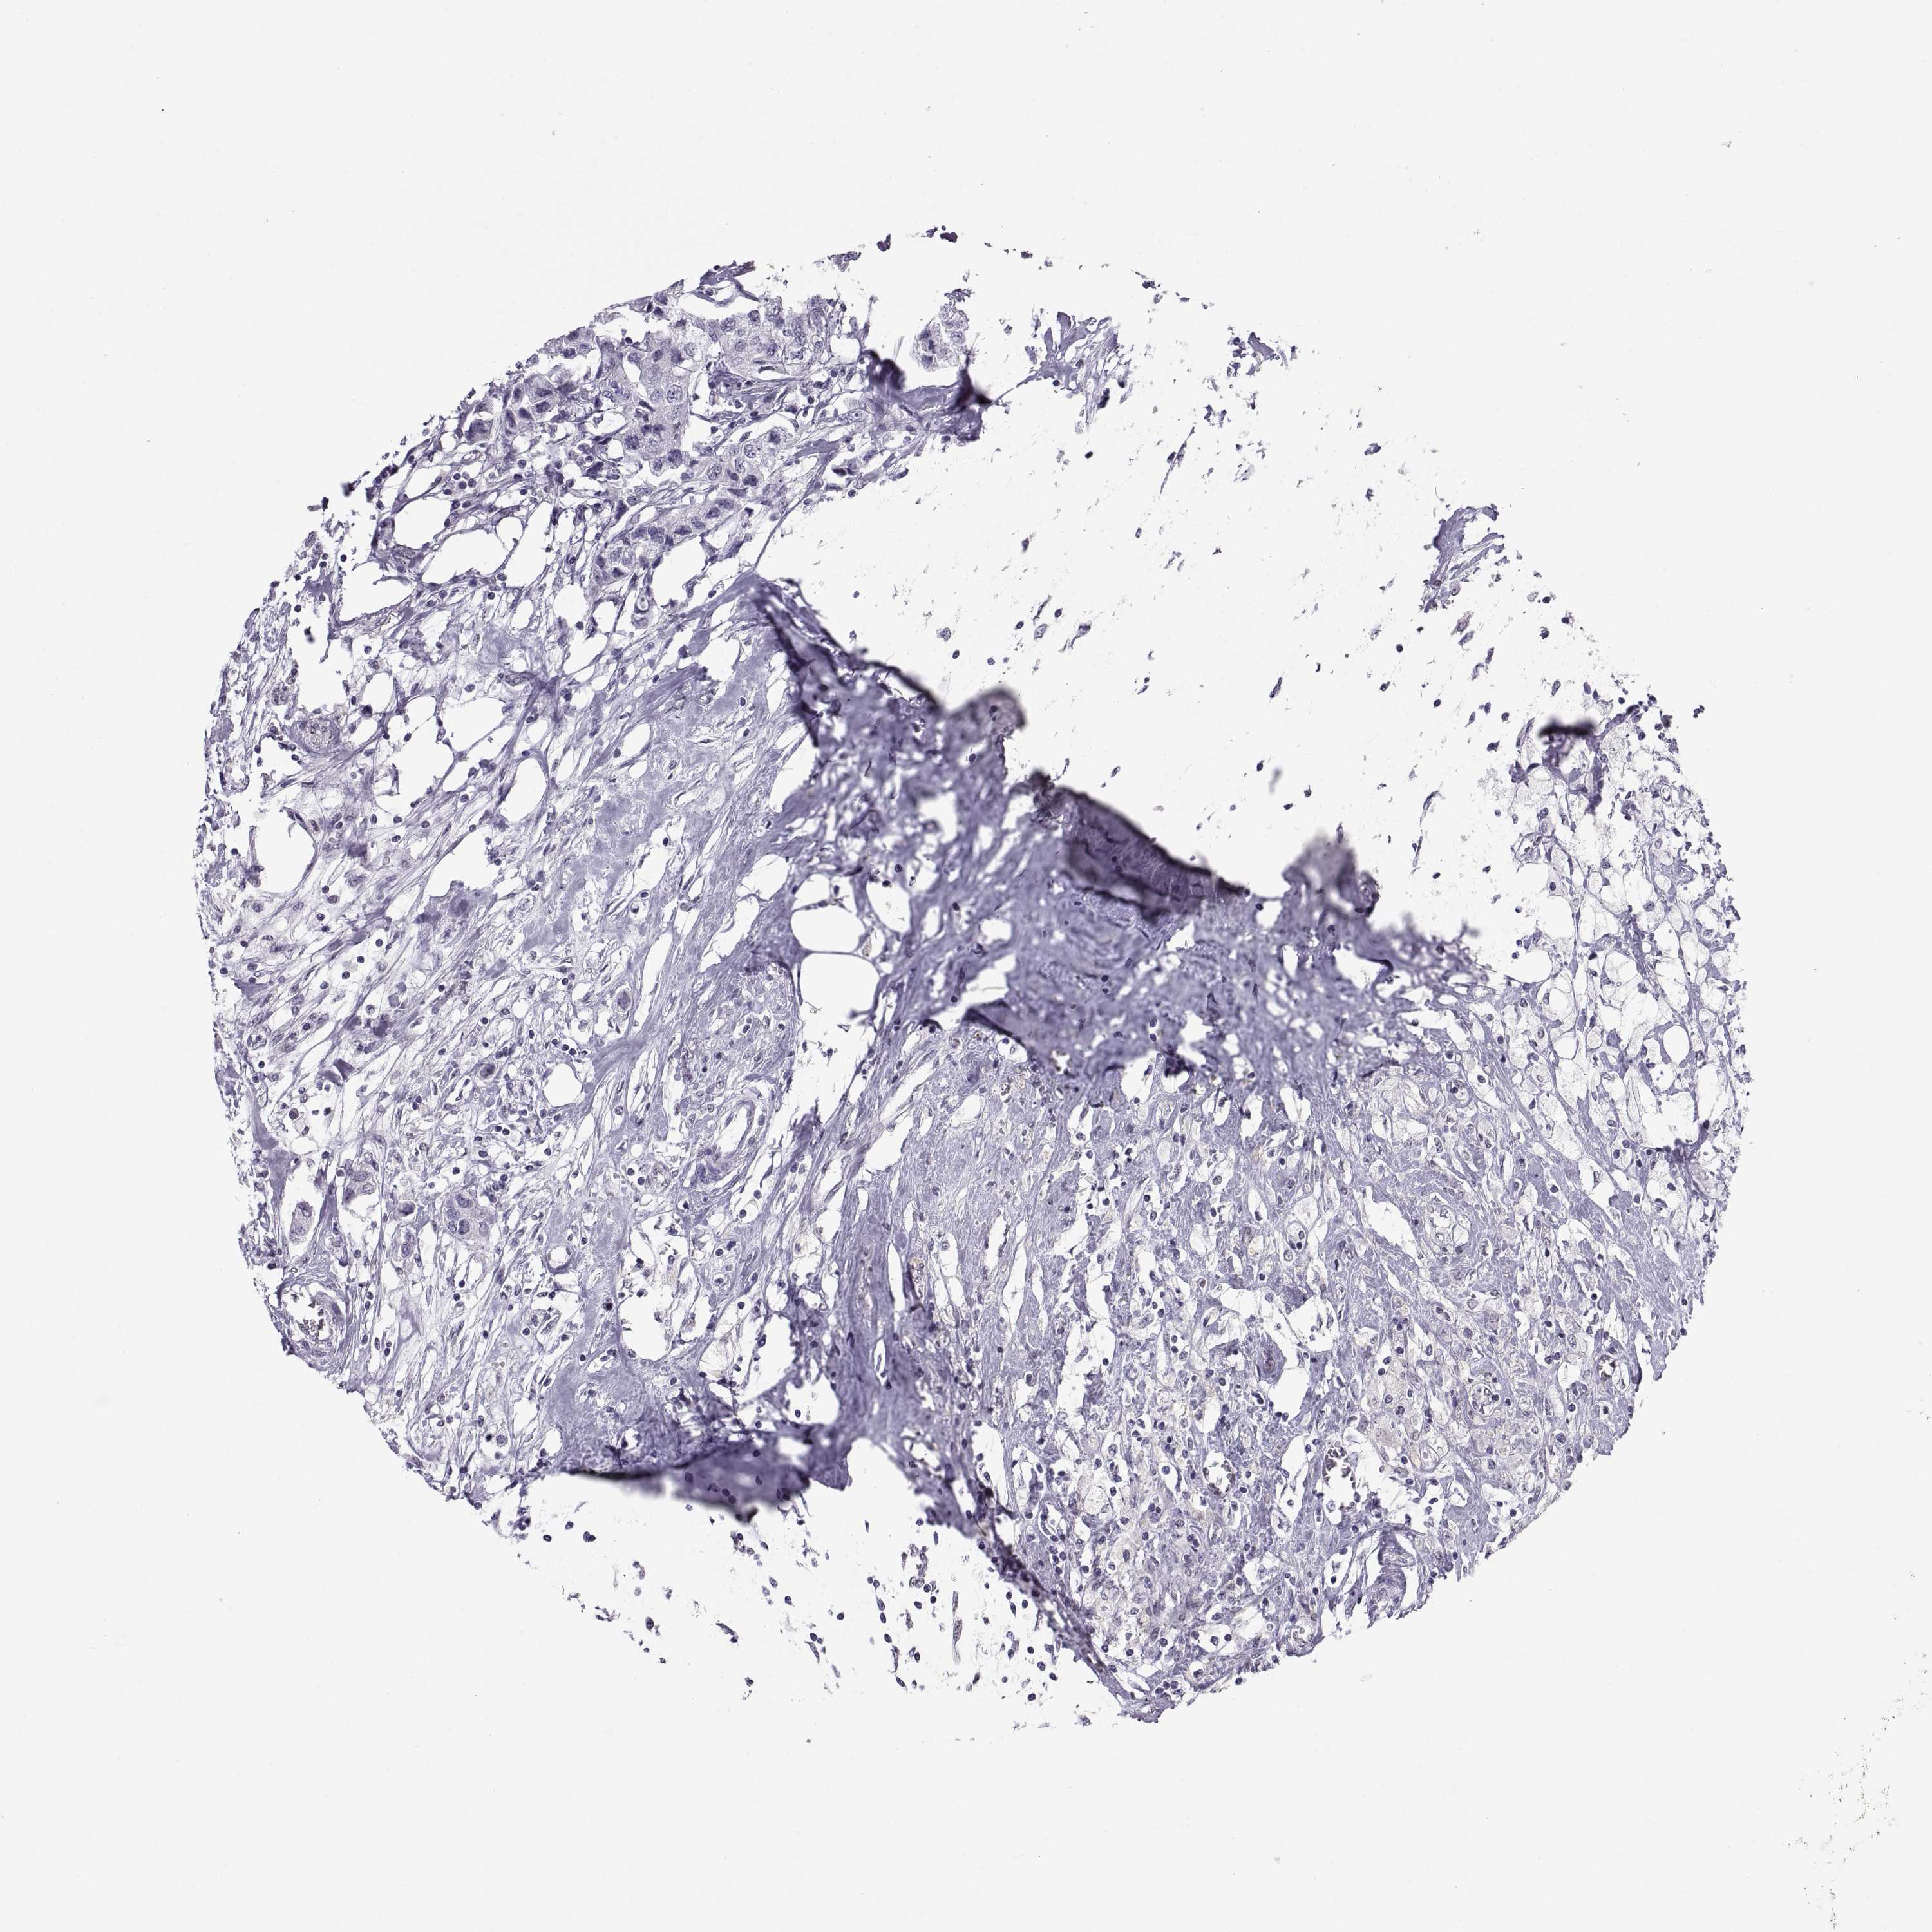

Breast cancer

Human cancer